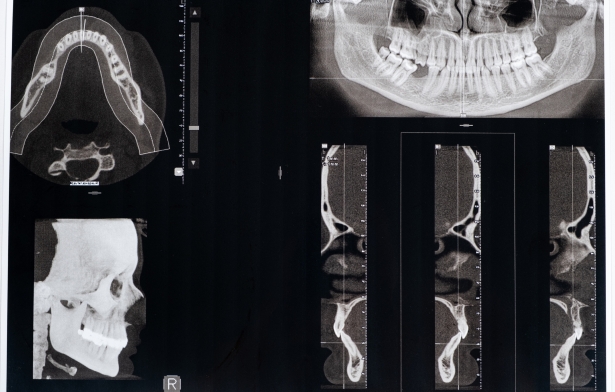

Hình ảnh chụp MRI thể hiện rõ các chi tiết như dây chằng, cơ, dây thần kinh